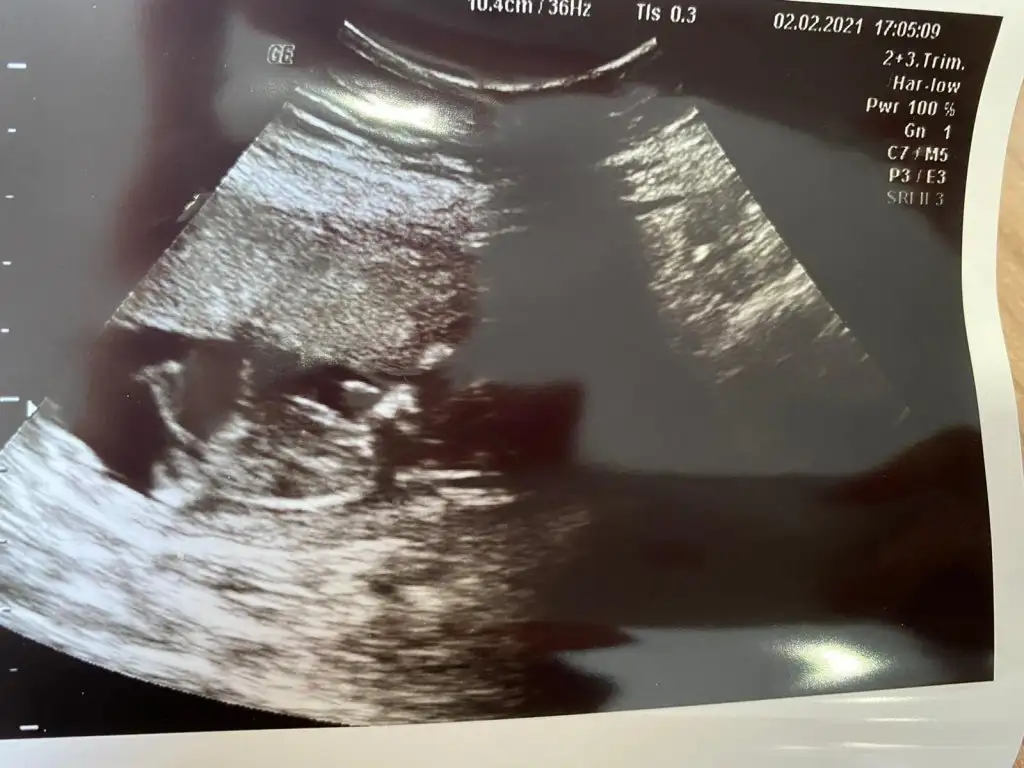

11+2 de ki karından ultrason görüntümüz bir şeyler gören varsa yazabilir mi? 😊

• WhatsApp Image 2021-02-03 at 11.18.20.webp

WhatsApp Image 2021-02-03 at 11.18.20.webp

32,8 KB · Görüntüleme: 206